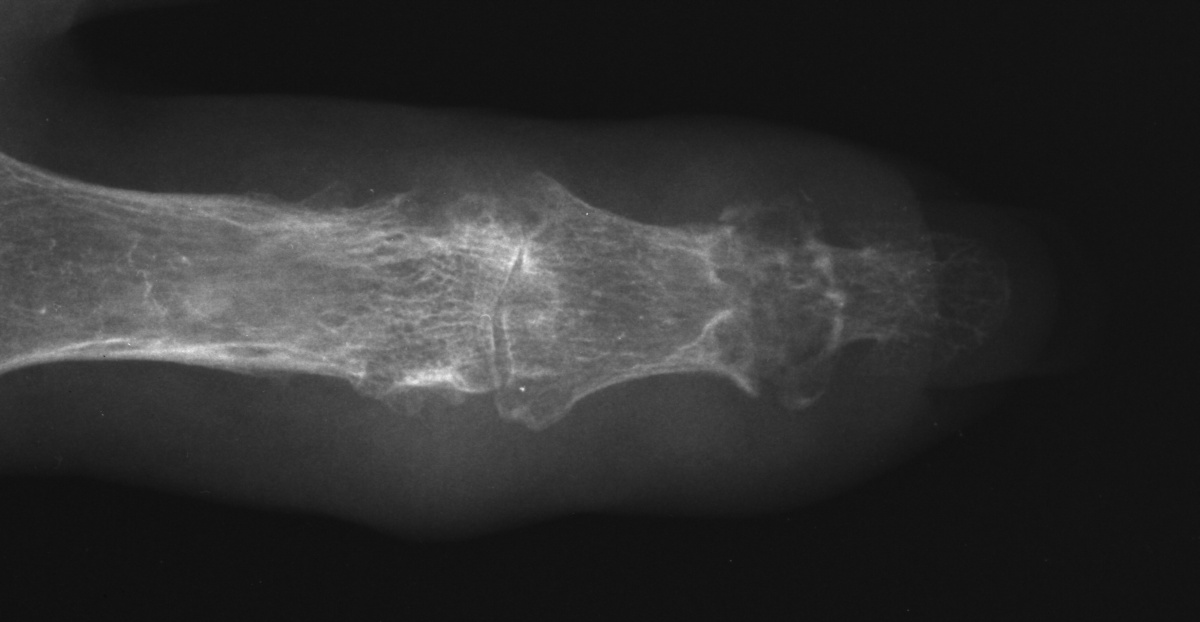

| Left index distal

interphalangeal joint tophus with thin overlying skin and nail

deformity. |

| Despite extensive

remodelling, the joint had 50 degrees of active motion. |